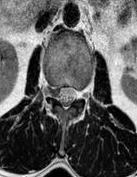

摘要:目的 分析计算机体层摄影血管造影(CTA)在腹腔镜结肠癌根治术前评估中的应用效果。方法 回顾性分析2021年1月-2024年2月于该院接受腹腔镜结肠癌根治术的120例患者的临床资料。其中,60例行常规腹部CT和CTA,60例行磁共振成像(MRI)。以术后病理为金标准,判断CTA对临床T分期与术后病理的一致性,以及评估肿瘤是否侵犯肠系膜血管和周围组织的准确度。结果 术前CTA诊断T分期的准确率为95.00%(57/60),一致性好(Kappa = 0.925,P < 0.05);术前MRI诊断结肠癌T分期的准确率为98.33%(59/60),两者比较,差异无统计学意义(χ2 = 0.26,P > 0.05)。CTA预判肿瘤是否累及肠系膜上动脉、肠系膜上静脉、肠系膜下动脉、肠系膜下静脉、腹主动脉、肾动脉、肾静脉和脾动脉等血管,与术后病理的一致性好。特别是在预测肠系膜血管受累方面,CTA的敏感度为94.44%,特异度为95.83%,准确度高达95.00%。结论 对于行腹腔镜结肠癌根治术的患者,术前CTA不仅能清晰地显示结肠癌T分期,还能揭示肠系膜血管的走行和变异,以及肿瘤与周围组织的关系和侵犯程度,从而为手术规划提供强有力的支持,确保了腹腔镜手术的安全性,减少了不必要的手术风险。